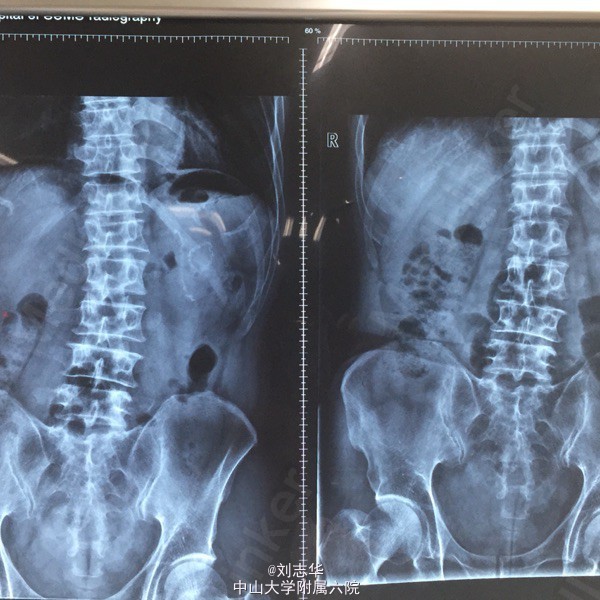

患者男,64岁,两年前于外院因"胃溃疡穿孔"行"胃大部切除术"。一天前无明显诱因出现上腹疼痛,程度剧烈,刀割样,急诊行腹平片检查:双膈下游离气体。

查体:上腹部10cm手术疤痕,全腹压痛反跳痛明显。肠鸣音1-2次/分。余无特殊。 腹平片:双膈下游离气体。